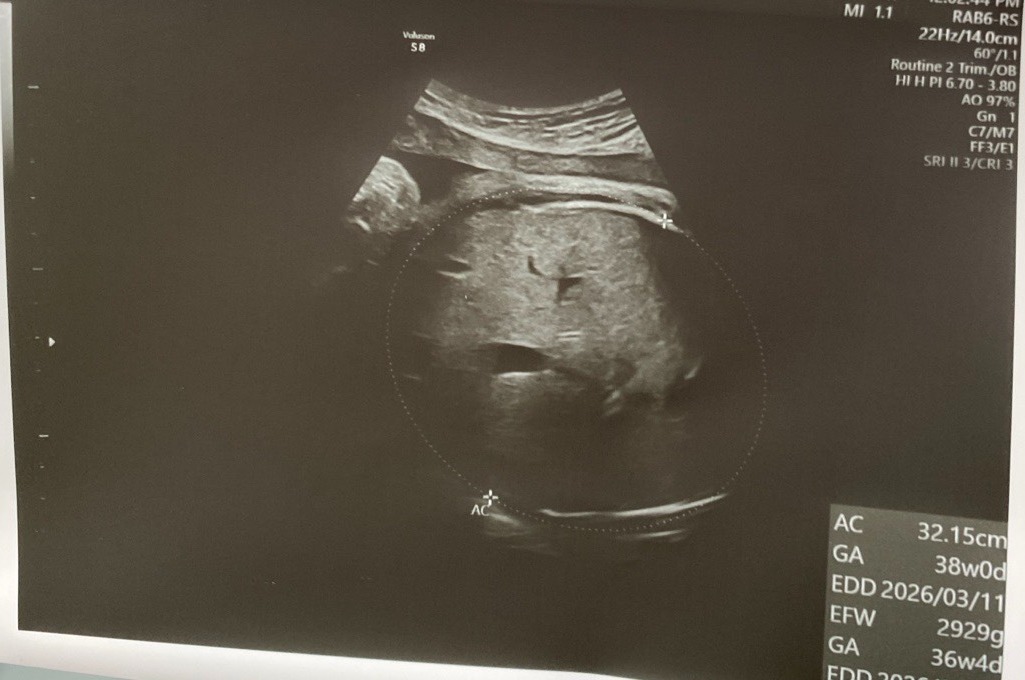

最後,三月即將迎接兩位新生命的來到,一起祝福兩位母親能順利生產, 也將這份喜悅與您分享。